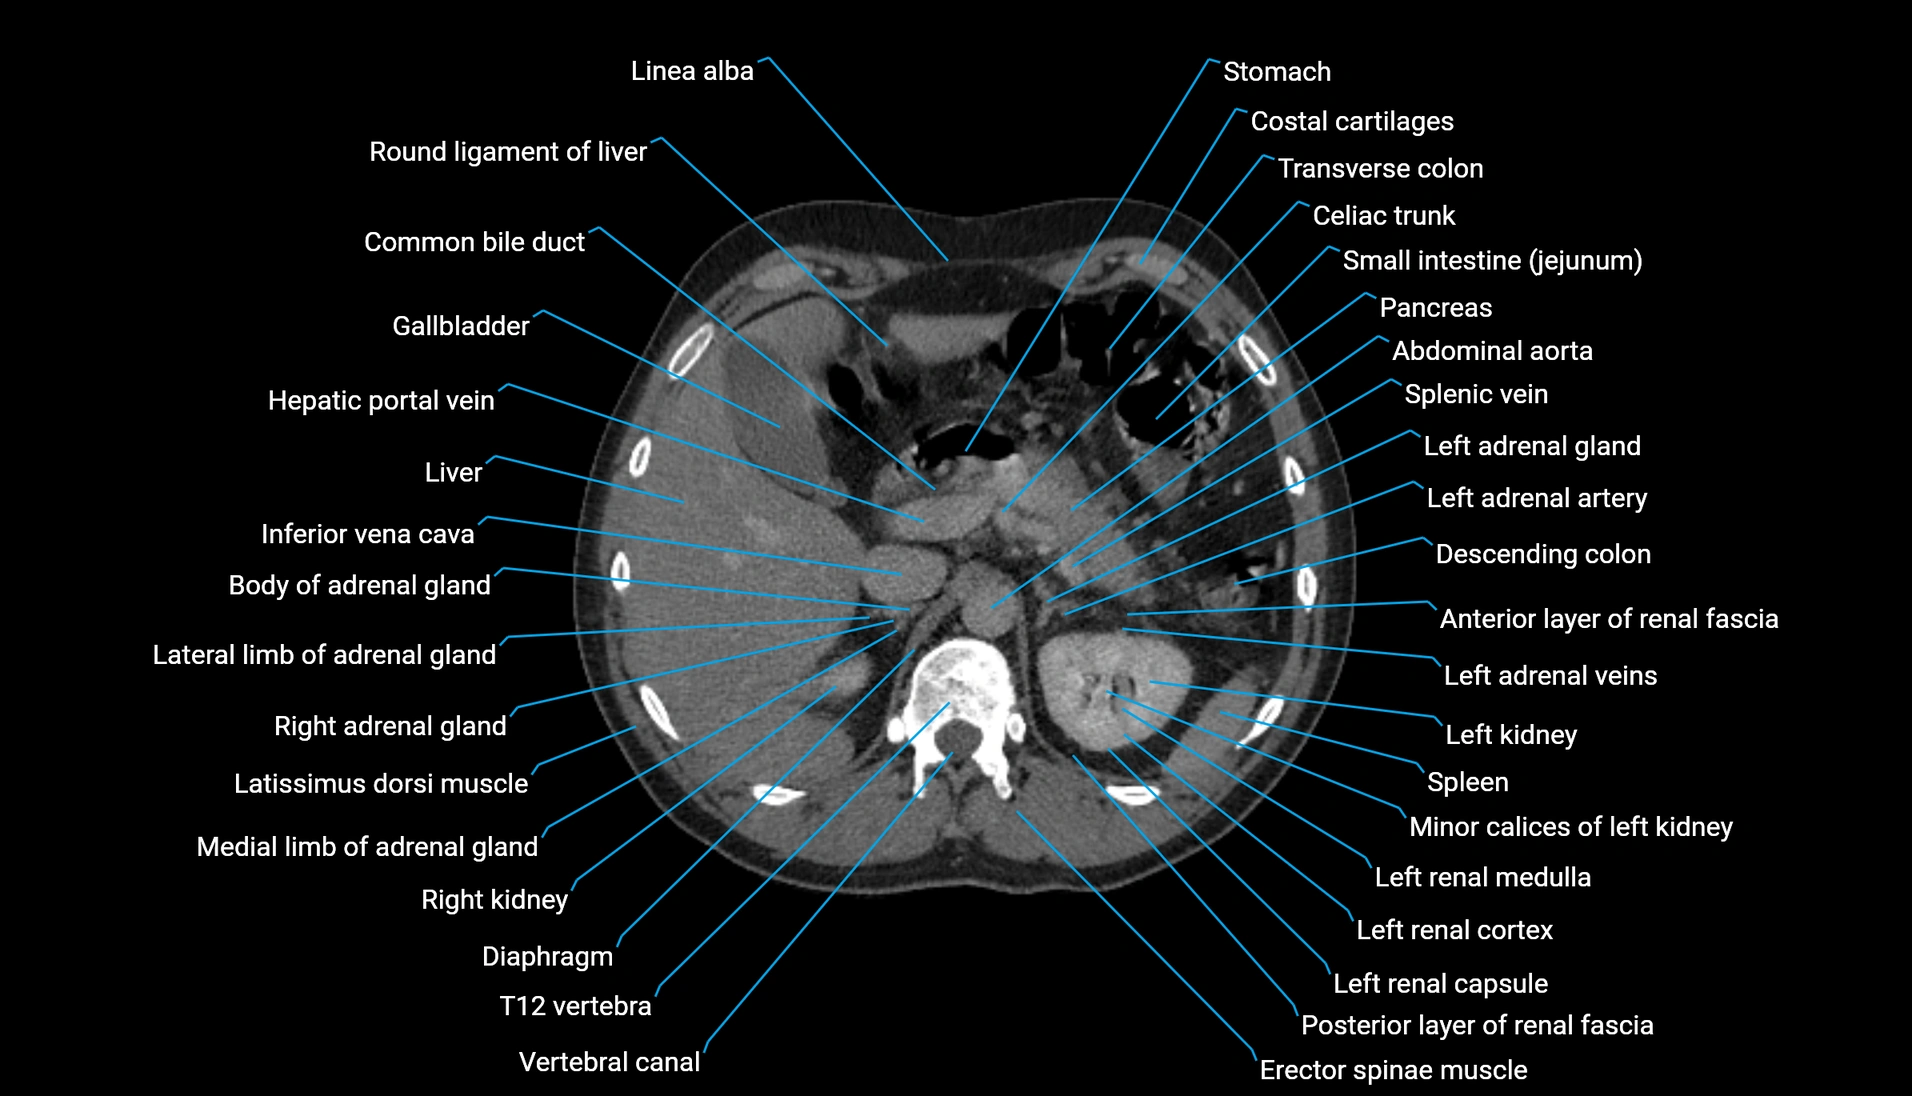

CT Appearance

Non-contrast CT:

-

Demonstrates cortical bone of acetabular rim in excellent detail

Detects fractures, dysplasia, retroversion, or bony overcoverage (pincer impingement)

3D reconstructions used in preoperative hip surgery planning

CT VRT 3D image

CT image